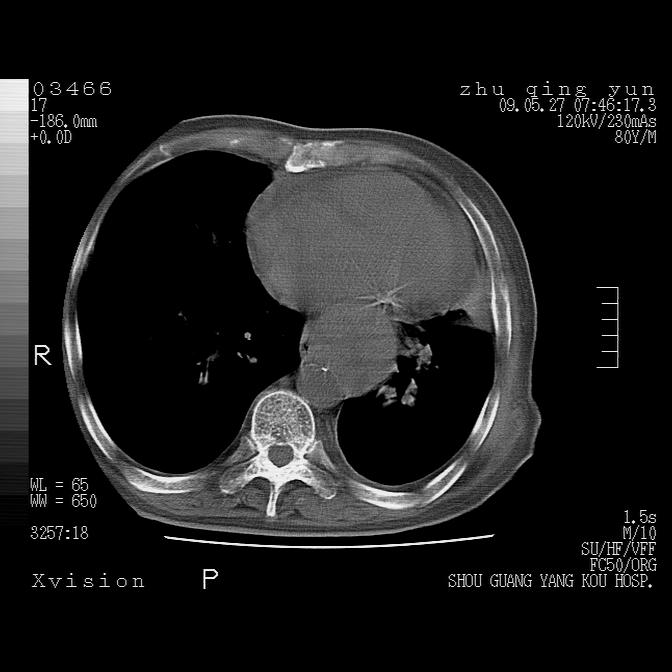

病人男性,年龄80,气喘来院,其他病史不太详细,1月前有过恶心,呕吐,在当地人民医院做过钡餐,诊断胃炎,

1)考虑左肺中央型肺癌并阻塞性肺炎,后下纵隔受侵伴纵隔淋巴结转移。2)双侧少量胸腔积液,胸膜增厚。3)心包积液。

左肺下叶见多发片状及结节状病灶,左肺基底段支气管闭塞,纵隔内见多发淋巴结肿大,纵隔向左侧移位,左侧胸廓变小。应该是左肺下叶中心型肺癌,纵隔淋巴结转移,左侧肺内转移,左肺基底段肺不张,阻塞性肺炎。

1)考虑左肺中央型肺癌并左肺下叶阻塞性肺炎、不张;左胸膜腔积液、心包积液、纵隔淋巴结转移;癌肿累及左心房。2)左心室大。冠状动脉壁钙化斑。

1)考虑左肺中央型肺癌并左肺下叶阻塞性肺炎、不张;左胸膜腔积液、心包积液、纵隔淋巴结转移;癌肿累及左心房。